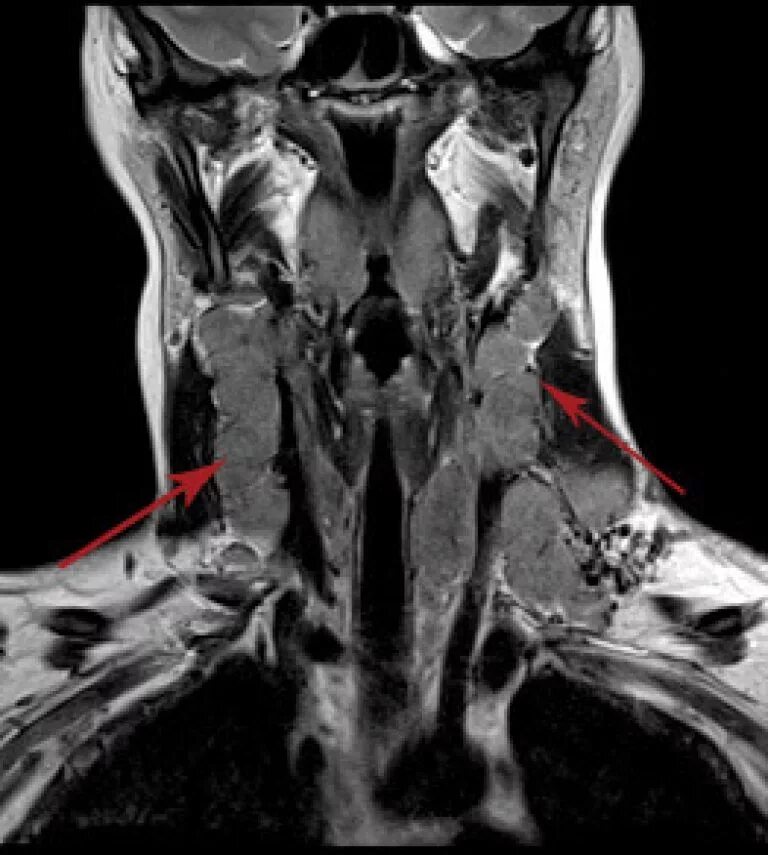

Кт тканей